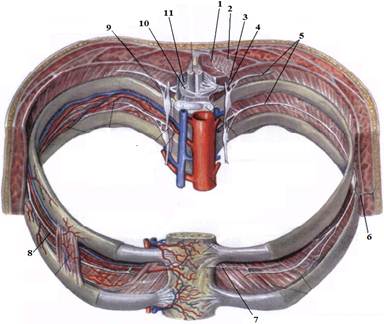

1. Яким номером позначено N. thoracicus?

2. Яким номером позначено N. intercostalis?

3. Яким номером позначено R. cutaneus lateralis?

4. Яким номером позначено R. dorsalis n. thoracici?

5. Яким номером позначено R. cutaneus lateralis r.dorsalis n. thoracici?

6. Яким номером позначено R. cutaneus medialis r.dorsalis n. thoracici?

7. Яким номером позначено R. cutaneus anterior?

8. Яким номером позначено Rr.communicantes n. thoracici?

9. Яким номером позначено Radix dorsalis n. thoracici?

10. Яким номером позначено Radix ventralis n. thoracici?

На таблицях і трупах студенти знаходять судинно-нервового пучка міжребрового проміжку. Далі на трупі розглядають хід і розподіл грудних нервів та ділянки їх інервації, Користуючись таблицями вивчають лімфатичні судини і вузли грудної клітки. На трупі ззаду і справа від грудної аорти знаходять грудну протоку. Визначають її корені хід топографію. На таблицях вивчають корені правої лімфатичної протоки визначають ділянки відпливу до двох головних лімфатичних проток.Викладач консультує студентів по темі заняття, показує незрозумілі деталі будови. В кінці заняття викладач шляхом тестування кінцевого рівня знань та вмінь оцінює роботу кожного студента в академічному журналі.